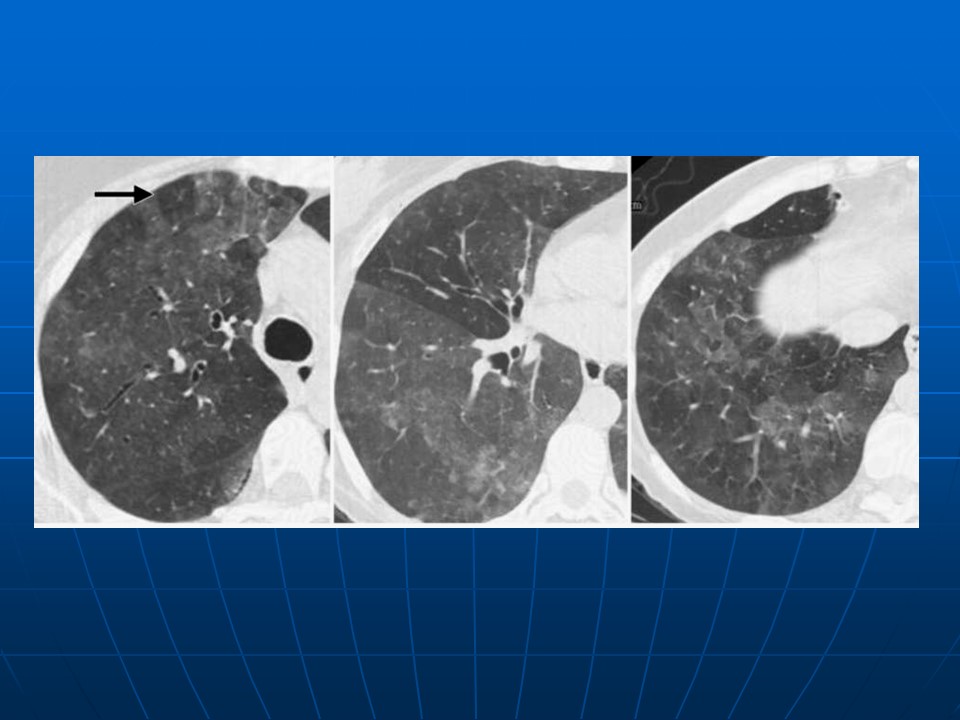

【PPT】早期肺癌易漏诊征象分析